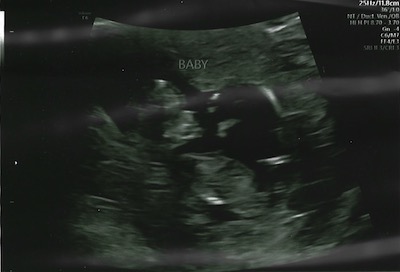

I got to see you again at 11 weeks.

I couldn't believe how much you had grown and that now you were looking more like a baby! We had plenty of scares, but we were always excited to see you grow.